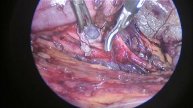

Обрезание крайней плоти. Циркумцизия. Случай #39. Без монтажа. Результат в следующем видео.

Вашему внимаю представлена операция циркумцизия. Хирург- Шахбанов Ильяс Усманович. Номер для консультаций +79677488100. Запись на консультацию через сайт ПроДокторов (выбрать город Химки) или DocDoc. Видео операции без видеомонтажа (монтажу подвергнута звуковая дорожка, удалены фрагменты где звучит голос пациента).

Видео Обрезание крайней плоти. Циркумцизия. Случай #39. Без монтажа. Результат в следующем видео. автора Врач-уролог Шахбанов Ильяс Усманович